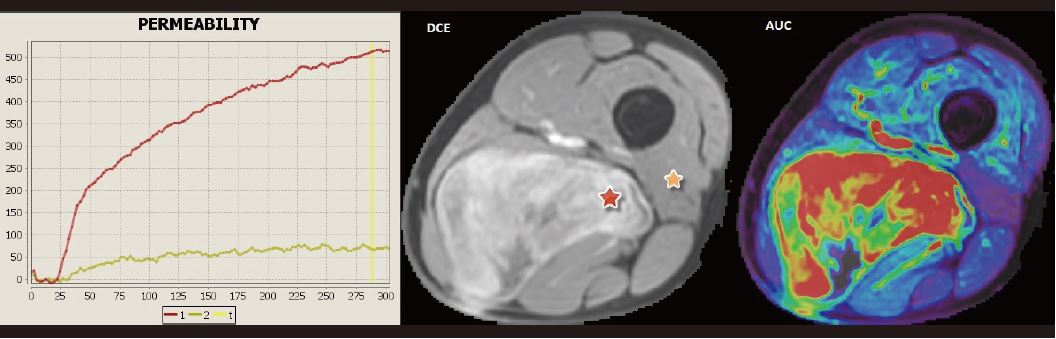

Багатопараметричний аналіз надає додаткову інформацію про структуру, васкуляризацію та їх зміни під час лікування. У цьому випадку міксоїдної ліпосаркоми (рідкісна пухлина м’яких тканин з оманливим доброякісним виглядом) (рис. 3) порівняння між пухлиною та здоровим м’язом можна здійснити на основі поглинання контрастної речовини та аналізу кінетики. Тут відзначається швидке посилення контрасту з наступним безперервним посиленням без вимивання, що добре відомо для пухлин із великим діапазоном інтерстиціальної тканини. Ці знахідки характерні для таких пухлин.

Кількісний аналіз перфузії T1 (DCE) базується на застосуванні фармакокінетичної моделі між внутрішньо- та позасудинним позаклітинним простором.

Моніторинг параметра Ktrans (константа переносу плазми в позаклітинний простір) дозволяє відобразити хорошу відповідь на хіміотерапію.

Рисунок 3